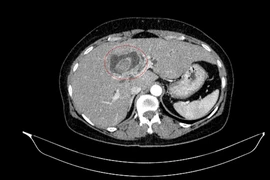

Theo Bệnh viện Nhi Thanh Hóa, rò xoang lê là bệnh lý bẩm sinh do còn tồn tại túi mang III, IV từ thời kỳ bào thai. Ở Việt Nam rò xoang lê chiếm tỷ lệ rất cao 51.92 – 73.68% trong các bệnh lý nang và rò mang bẩm sinh vùng cổ bên.

Bệnh này thường khởi phát chủ yếu ở trẻ em với biểu hiện u nang vùng cổ bên, áp xe vùng cổ tái diễn nhiều lần, sưng tấy, áp xe vùng tuyến giáp nên dễ nhầm với áp xe tuyến giáp, viêm tuyến giáp cấp mủ, áp xe hạch.